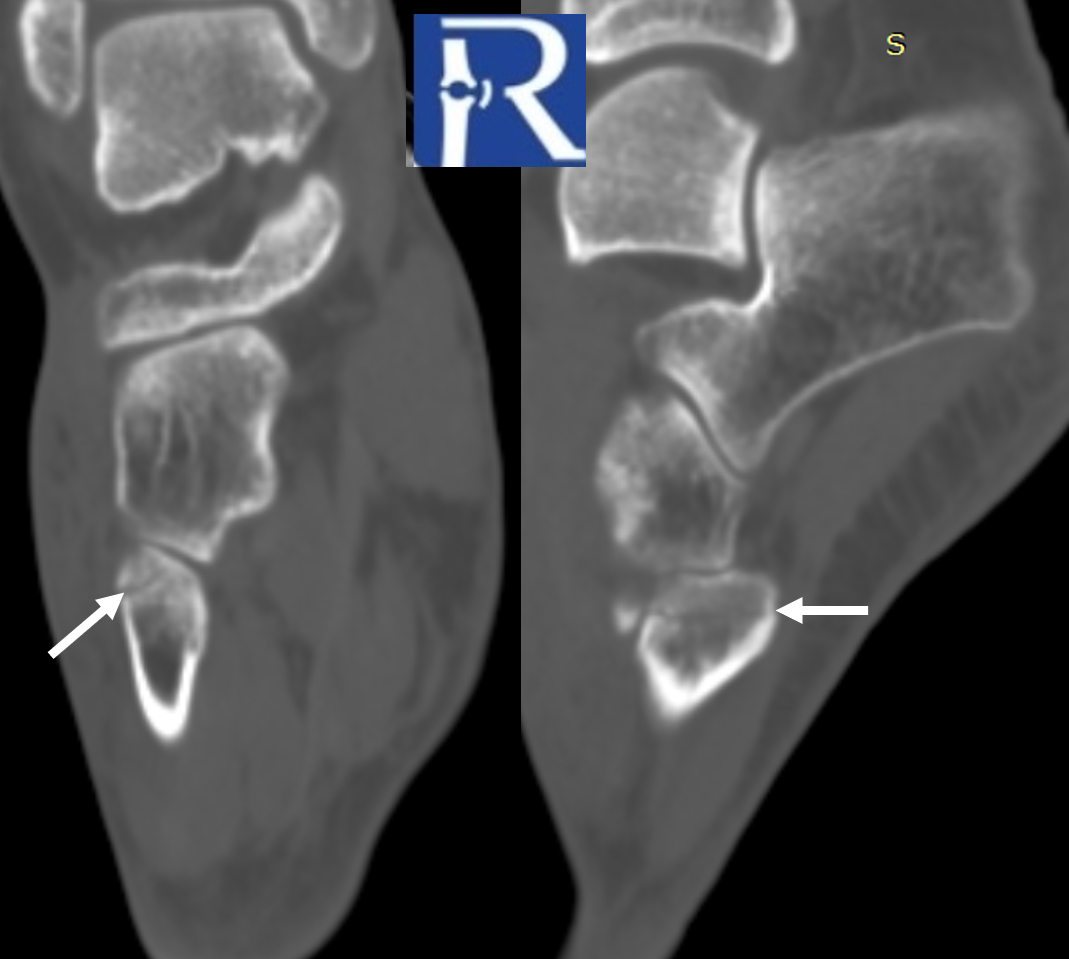

A foot radiograph revealed a suspicious radiolucency at the base of the 5th metatarsal (zone I). CT demonstrated a subtle fracture line on axial slices (indicated by white arrows). On reformatted sagittal and coronal planes, the non-displaced fracture line was clearly visible (white arrows), consistent with a pseudo-Jones fracture. Because the fracture can appear equivocal on plain radiographs and axial CT slices, long-axis reconstructions are essential for accurate evaluation in trauma patients.

For optimal fracture assessment, extremity CT scans should always be reviewed in all three planes.

Pseudo-Jones fractures typically appear as a transverse or oblique radiolucent line at the base of the 5th metatarsal tuberosity (zone I, purple), often associated with cortical step-off or minimal displacement. On plain radiographs, they may be subtle and can be obscured by overlapping structures, leading to underdiagnosis. CT, particularly with multiplanar reformations, improves detection by delineating the fracture line and ruling out intra-articular extension. MRI is not routinely required but can demonstrate associated marrow edema when the fracture is radiographically occult. Importantly, differentiation from true Jones fractures, which occur at the metaphyseal–diaphyseal junction (zone II, yellow), and stress fractures, typically arising in the proximal diaphysis (zone III, blue), is crucial, as treatment strategies and healing potential vary significantly between these entities.